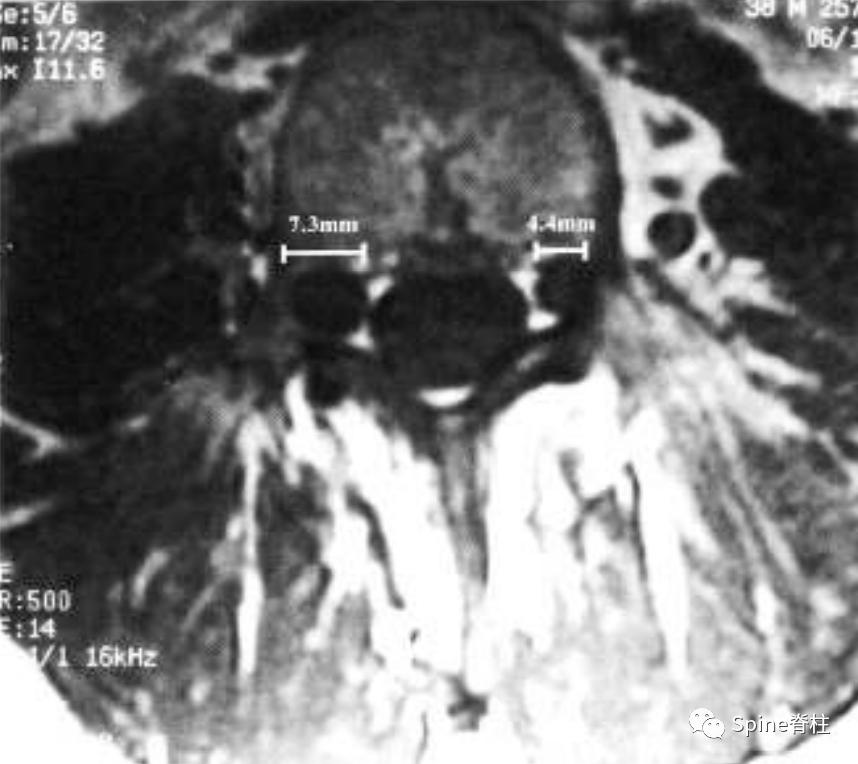

矢状位T2(a)和T1(b)加权像提示下胸椎和上腰椎硬膜扩张伴显著的椎体后壁扇形凹陷(红色箭头)。轴位T2(c)和T1(d)加权像提示硬膜囊外侧膨出(绿色箭头)伴椎体扇形缺损。蓝色箭头是指继发于皮肤神经纤维瘤的多发性皮肤结节